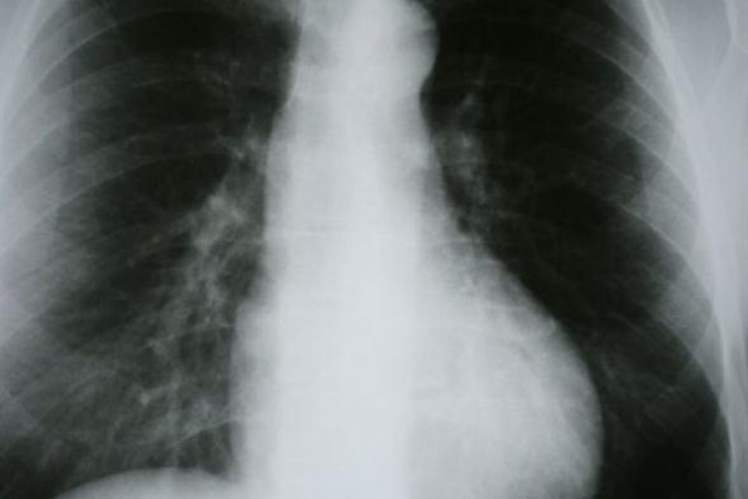

'KOAH'ın en ciddi riski sigara'

'Hastaların yüzde 90'ı KOAH olduğunun farkında değil'